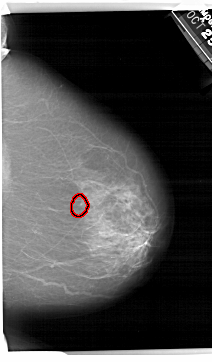

A_1495_1.LEFT_MLO

LEFT_MLO LINES 6811 PIXELS_PER_LINE 4066 BITS_PER_PIXEL 12 RESOLUTION 43.5 NON_OVERLAY

FILE: A_1495_1.RIGHT_MLO.OVERLAY

TOTAL_ABNORMALITIES 1

ABNORMALITY 1

LESION_TYPE CALCIFICATION TYPE AMORPHOUS DISTRIBUTION CLUSTERED

ASSESSMENT 4

SUBTLETY 4

PATHOLOGY BENIGN

TOTAL_OUTLINES 1

BOUNDARY